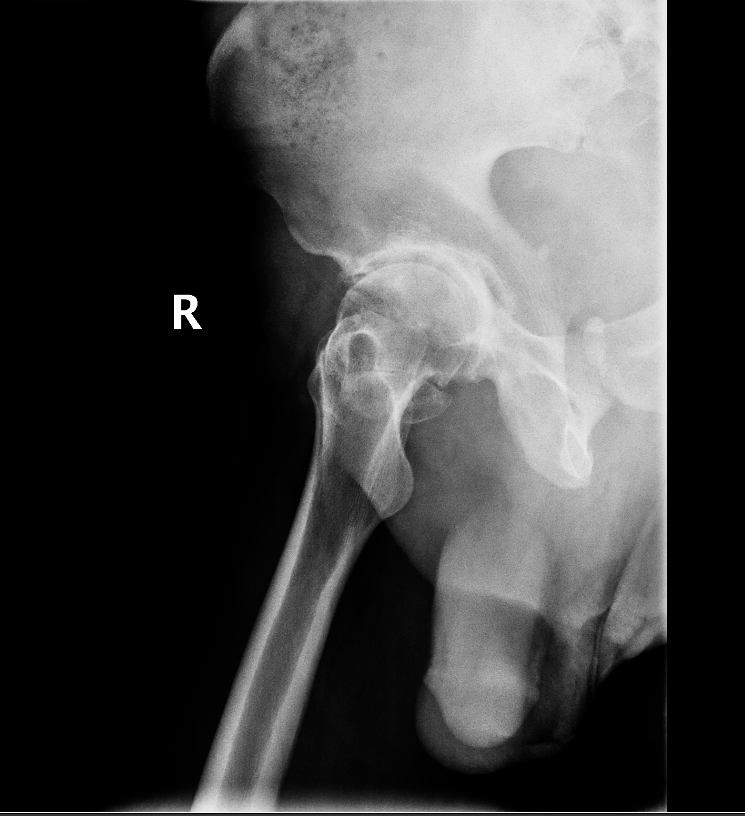

Diagnosis is made by evaluating medical history, physical examination and X-rays.

- Osteoarthritis: It is characterized by progressive wearing away of the cartilage of the joint. As the protective cartilage wears down, the bone ends rub against each other and cause pain in the hip. Rheumatoid arthritis: This is an autoimmune disease in which the tissue lining the joint (synovium) becomes inflamed, resulting in the production of excessive joint fluid (synovial fluid). This leads to loss of cartilage causing pain and stiffness.

- Traumatic arthritis: This is a type of arthritis resulting from a hip injury or fracture. Such injuries can damage the cartilage and cause hip pain and stiffness over a period of time.